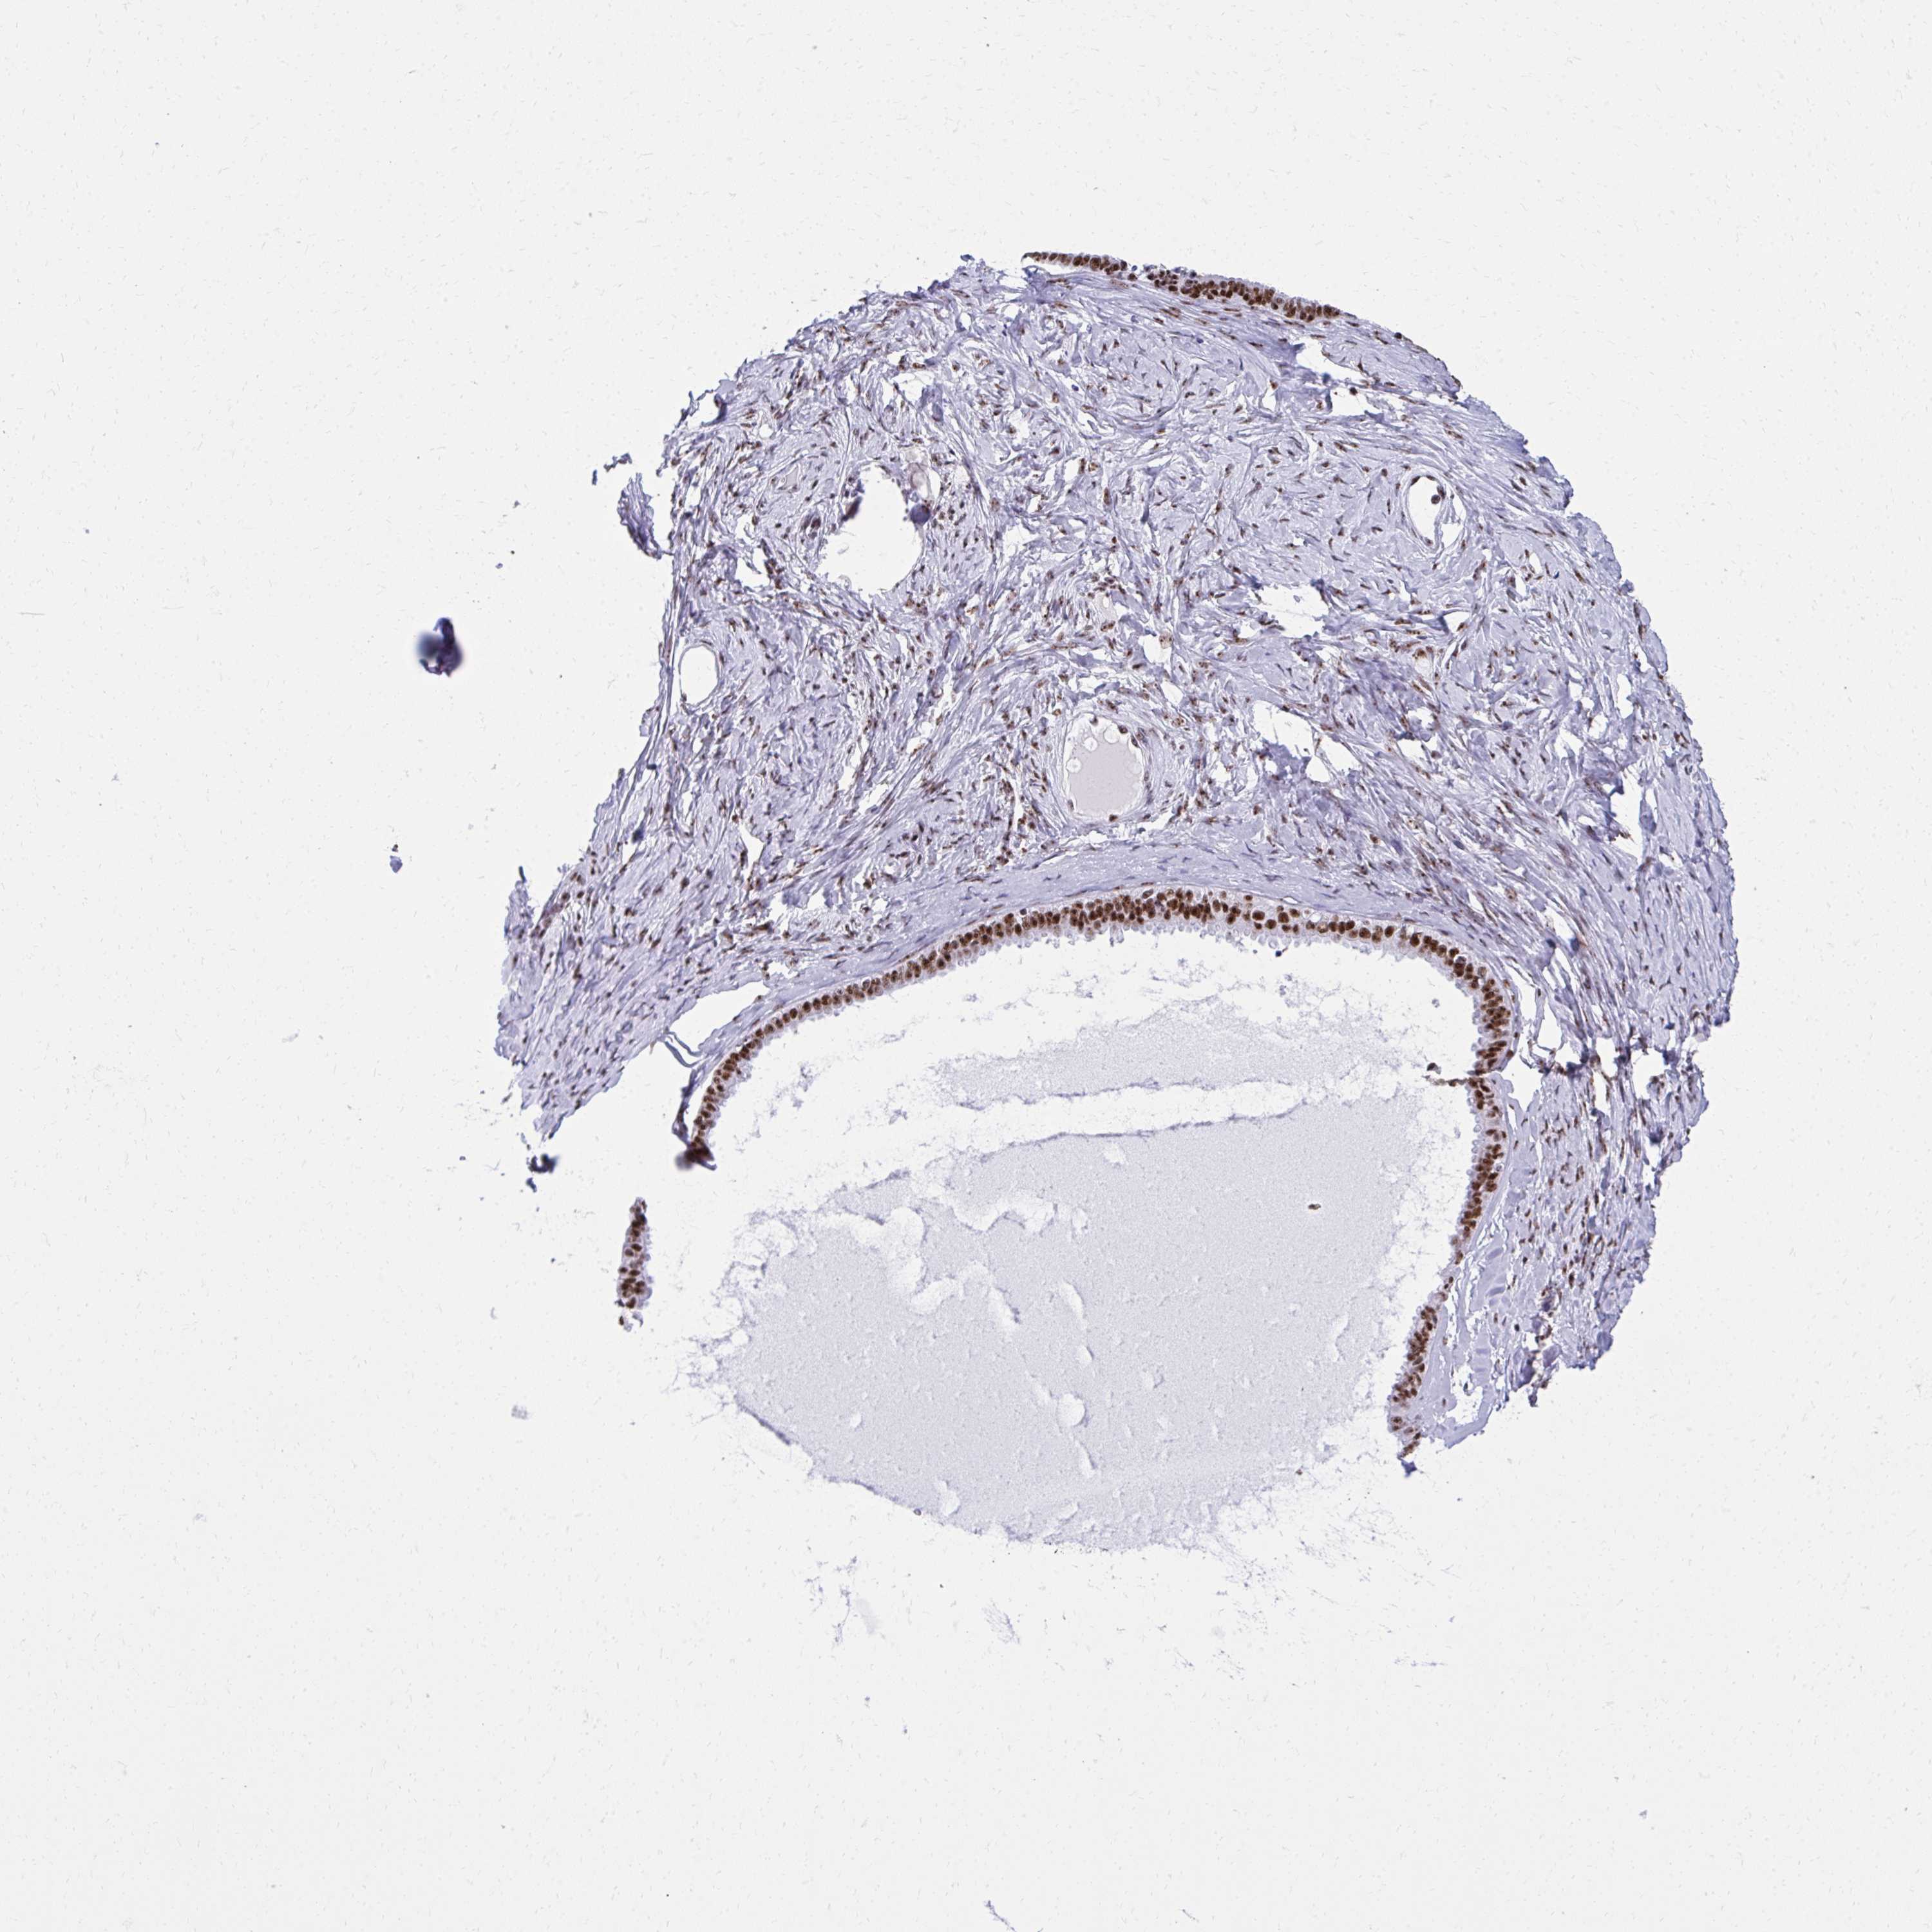

OVARIAN CANCER - Protein expressioni

A mouse-over function shows sample information and annotation data. Click on an image to view it in a full screen mode. Samples can be filtered based on level of antibody staining by selecting one or several of the following categories: high, medium, low and not detected. The assay and annotation is described here.

Note that samples used for immunohistochemistry by the Human Protein Atlas do not correspond to samples in the TCGA dataset.

Antibody stainingi

Antibody staining in the annotated cell types in the current human tissue is reported as not detected, low, medium, or high, based on conventional immunohistochemistry profiling in selected tissues. This score is based on the combination of the staining intensity and fraction of stained cells.

Each image is clickable and will lead to virtual microscopy that enables deeper exploration of all samples and also displays staining intensity scores, fraction scores and subcellular localization as well as patient and tissue information for each sample.

Antibody HPA060760

Staining

High

Medium

Low

Not detected

Intensity

Strong

Moderate

Weak

Negative

Quantity

>75%

75%-25%

<25%

None

Location

Nuclear

Cytoplasmic/membranous

Cytoplasmic/membranous,nuclear

Cystadenocarcinoma, serous, NOS

Cystadenocarcinoma, mucinous, NOS

Carcinoma, endometroid